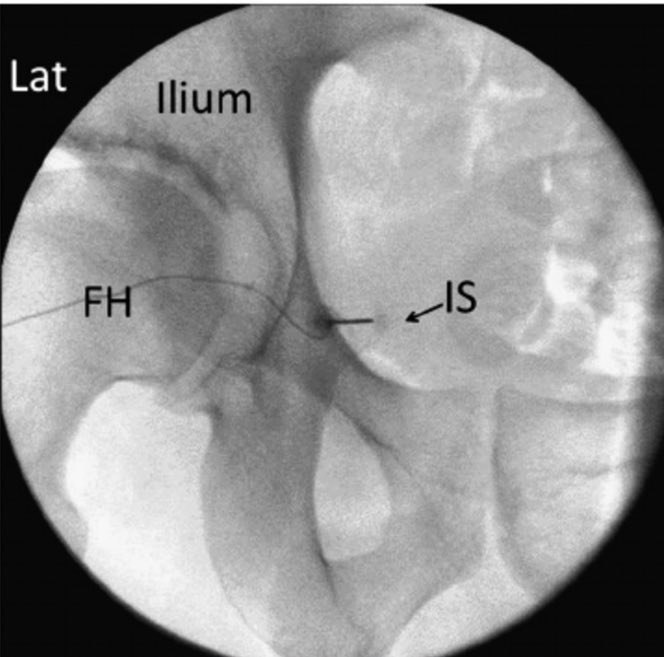

Innovando en el tratamiento del dolor pélvico crónico. Implante exitoso de electrodos de neuroestimulación Boston Scientific en nervios pudendos, bajo control ecográfico y radiológico. Mejoría del dolor en menos de 24 horas de un 90% #granequipo #siempreinnovando #dolorcrónico

[email protected] Boston Scientific Gracias Noelia 😊. La paciente italiana 61 a dolor neuropatico severo perineal , lo refería sobretodo anal y 1/3 externo vagina. Gran afectación ritmo intestinal, abuso de laxantes. 5 años de evolución y muchos especialistas previos. A. M. lo explica mejor que puso el derecho